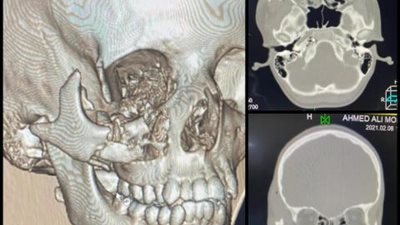

تفاصيل نجاح أول جراحة وجه وفكين بالتأمين الصحي بالأقصر

الثلاثاء 02/مارس/2021 - 01:30 م

أعلنت الهيئة العامة للرعاية الصحية نجاح أول جراحة وجه وفكين لترميم عظام الوجه وقاع العين لطفل يبلغ من العمر 14عام ا باستخدام تقنية الطباعة الطبية ثلاثية الأبع…